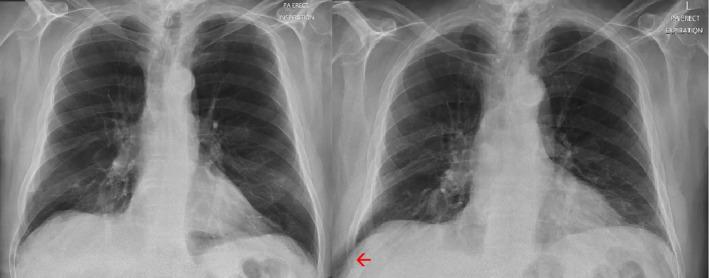

Spontaneous pulmonary hernia (SPH) is a rare condition. We report a case secondary to extreme coughing and COVID-19 infection. The patient displayed several clinical features typical of this diagnosis; difficult to manage pain on coughing, flank haematoma and bulging of the chest wall on coughing. Clinicians should be aware of the risk factors and clinical features of SPH to aid diagnosis of this rare condition.

自发性肺疝(SPH)是一种罕见的病症。我们报告一例继发于剧烈咳嗽和新型冠状病毒肺炎(COVID-19)感染的病例。该患者表现出了这种诊断的几种典型临床特征:咳嗽时难以控制的疼痛、胁腹血肿以及咳嗽时胸壁膨出。临床医生应了解自发性肺疝的危险因素和临床特征,以协助诊断这种罕见病症。